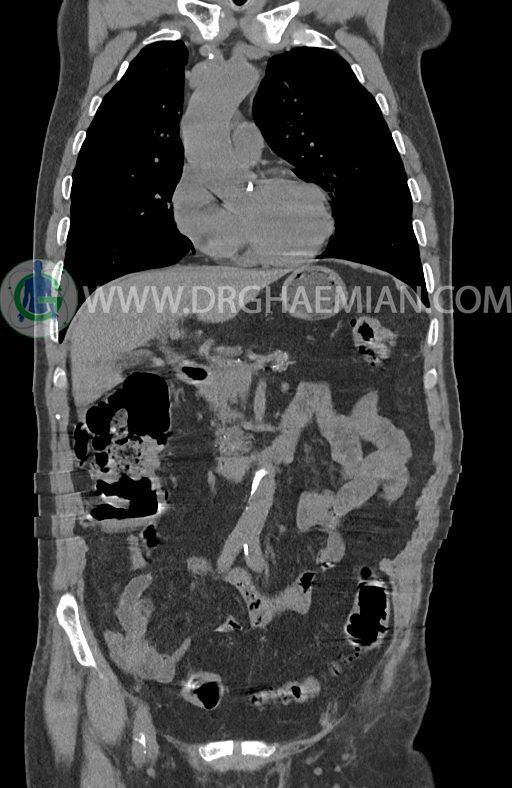

در سی تی اسکن اسپیرال ریه ها و مدیاستن، شکم و لگن با و بدون کنتراست وریدی (مولتی دیدکتور 16 با مقاطع ظریف و بازسازی کرونال) :

–افزایش ضخامت تومورال دیستال مری و GEJ در سگمانی به طول 4cm-5cm (T2 or T3)

–توده هیپودنس به قطر 10mm در پارانشیم طحال مشهود است. Quadriphasic MRI پیشنهاد می گردد.

–آتروفی نسبی پانکراس همراه با فوکوس های کلسیفیه ی منتشر پارانشیم مطرح کننده ی پانکراتیت مزمن

-CBD بسیار دیلاته (16mm) همراه با دیلاتاسیون مجاری داخل کبدی سنترال بدون شواهد سنگ یا توده در مسیر

–کیست های کورتیکال متعدد هر دو کلیه به بزرگترین قطر 56mm

نتیجه : T(2or3)/N2/M0